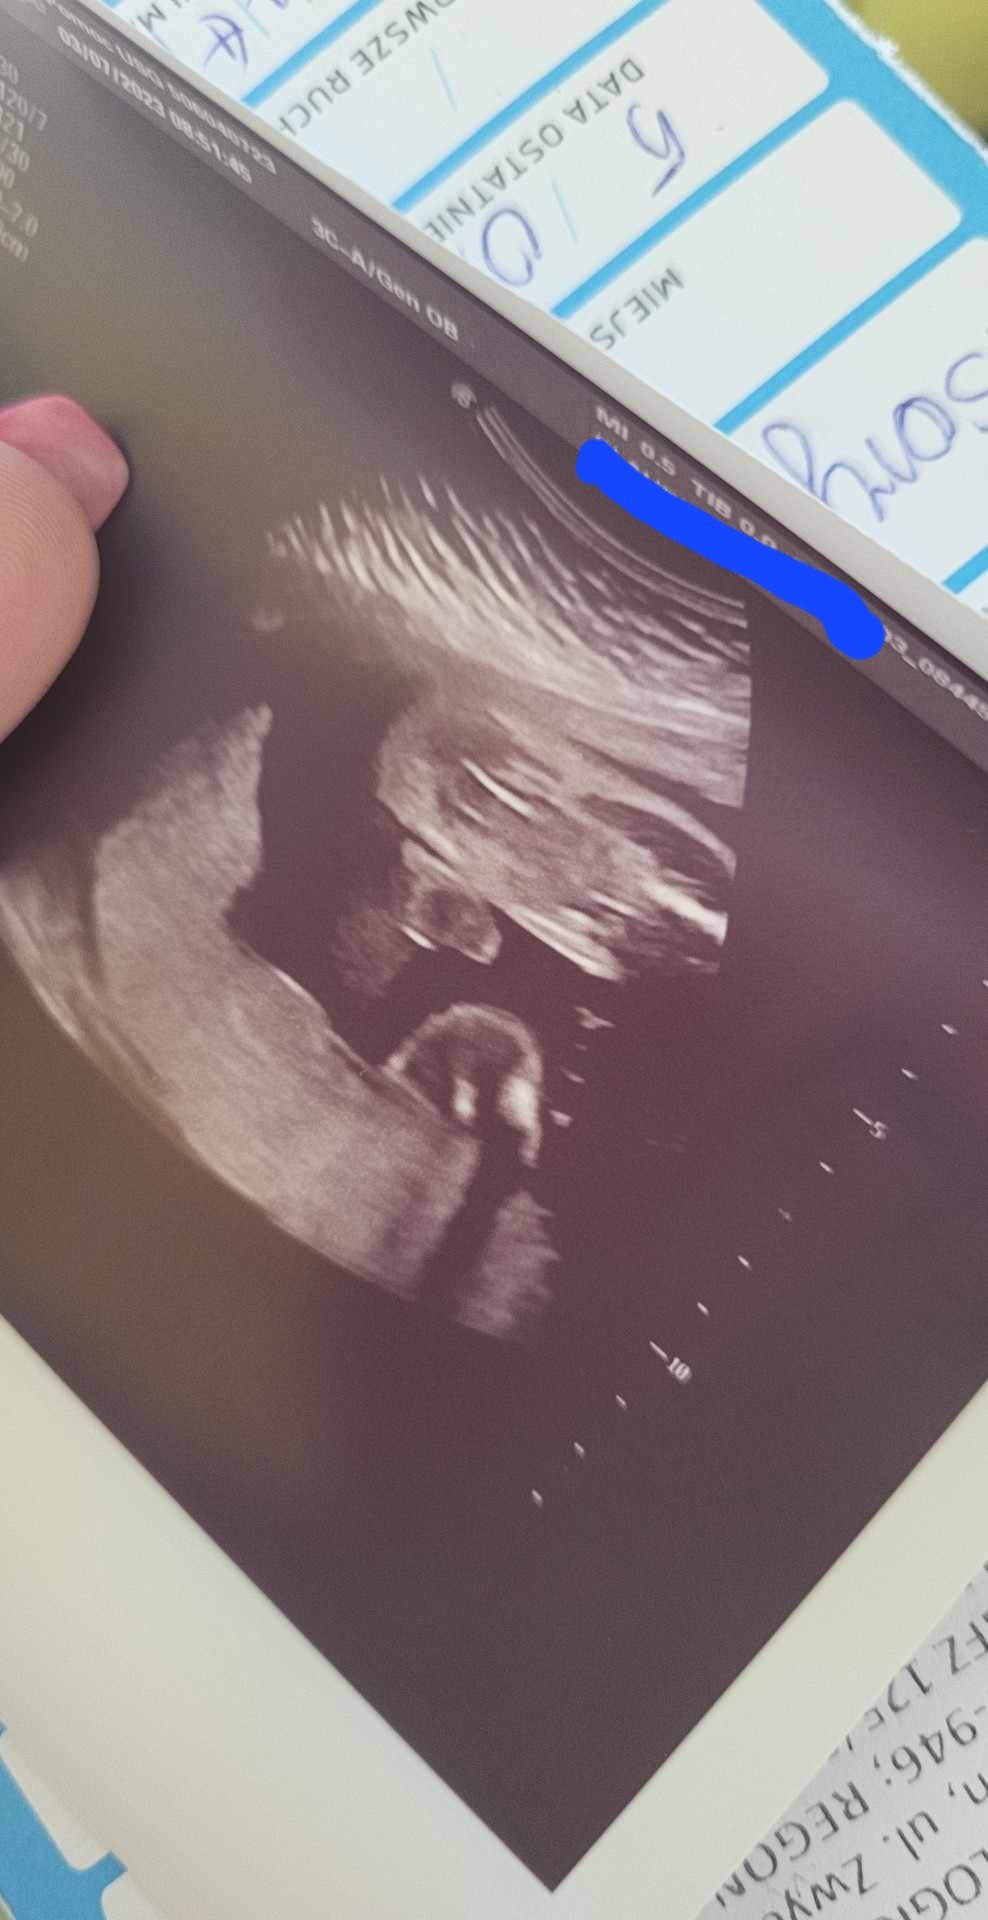

Dziękuję za odpowiedź :) a podesle jeszcze takie zdjecie : czyli możliwe zeby na tym to była pepowinka albo maleństwo cos podłożyło? :) Pani Doktor twierdzi, że w 24 tygodniu to powinny być już dobrze widoczne jajeczka a tu nie wygląda na to :)

Tak :) na pierwszych prenatalnych lekarz powiedział, że wygląda na to, że dziewczynka :) a na drugich właśnie ten sam lekarz, ze raczej chlopczyk i takie oto zdjęcie :)